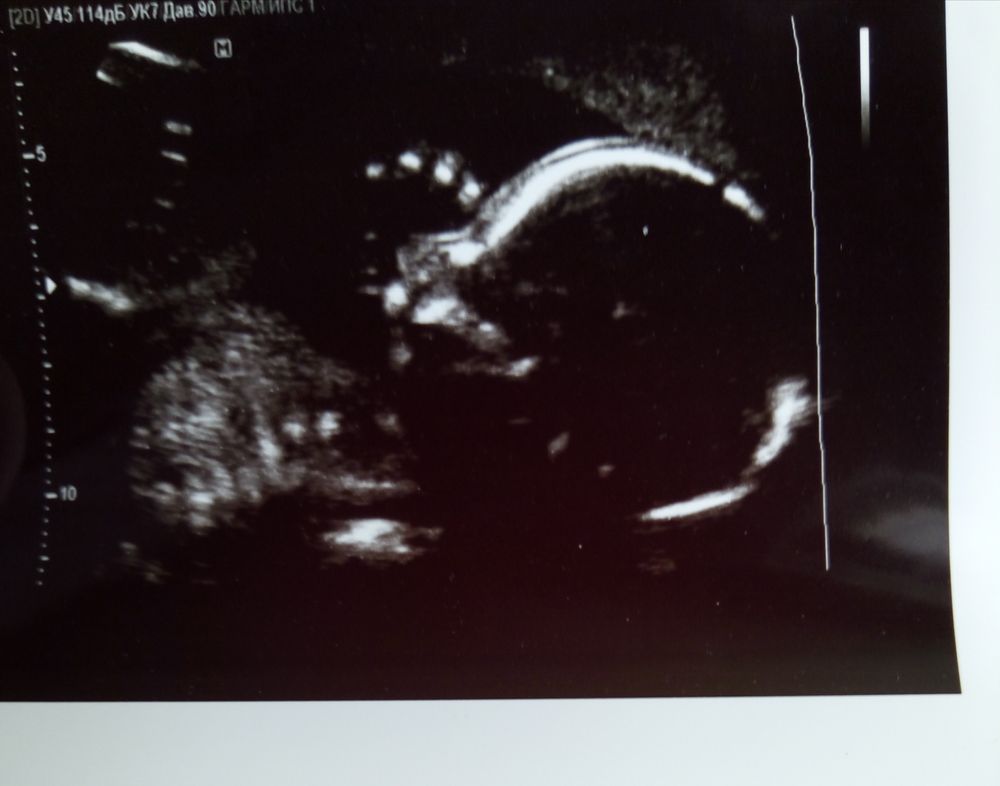

Девочки, посмотрите пожалуйста УЗИ фото, нет ли там намёка на СД?

Всё о нашей беременностиУЗИ в 20 недель фото в комментариях

Уже на 30 будет личико видно, ротик открыт... но мне кажется все ок будет, т к анализы хорошие

Ну по картинке вам не скажут, тут нужны замеры, и нужно с первого скрининга показатели воротникового пространства.